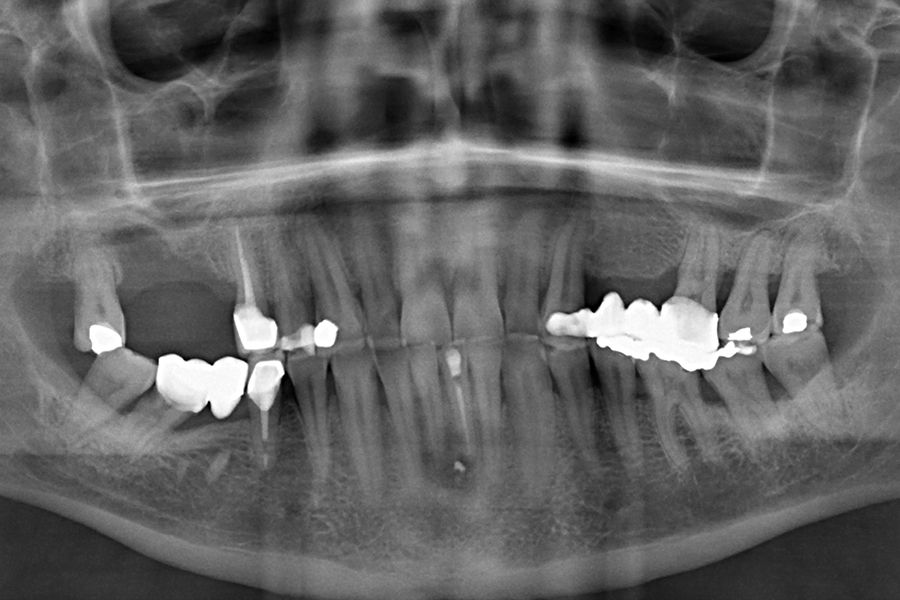

En las figuras 5-13 se muestra uno de los casos incluidos en el estudio.

La localización del evento adverso fue mayoritariamente en implantes situados en posición 26 (18,2%), seguido de localización 16 (13,6%), representando por lo tanto los primeros molares maxilares el 34,5% de todos los eventos registrados. El resto de las localizaciones donde se registraron incidencias mecánicas se muestran en la figura 2. Si agrupamos los eventos en maxilar superior o mandíbula, registramos una mayor incidencia en la parte superior con un 68% de los casos.

El IAH medio de todos los pacientes fue de 33,29 (+/- 18,90;rango 20-110). Si analizamos la presencia de eventos adversos en las prótesis en función del IAH, obtenemos que la mayor parte de los eventos adversos se concentran en los tramos mayores del IAH, tal como podemos observar

en la figura 4, aunque no se ha encontrado una correlación positiva entre el aumento del IAH y el tipo de complicación acontecido (p=0,432).